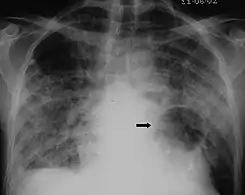

The diagnosis can be confirmed by the characteristic appearance of the chest X-ray and an arterial oxygen level (PaO2) that is strikingly lower than would be expected from symptoms. Gallium 67 scans are also useful in the diagnosis. They are abnormal in about 90% of cases and are often positive before the chest X-ray becomes abnormal. Chest X-ray typically shows widespread pulmonary infiltrates. CT scan may show pulmonary cysts (not to be confused with the cyst-forms of the pathogen).

X-ray of a cyst in pneumocystis pneumonia[7]